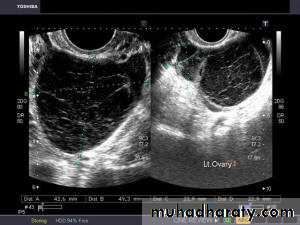

Lt. adnexal cystic mass- Luteal cyst(Lt. ovary):• Functional cysts of the ovary – Corpus Luteum cysts

Rt. ovarian simple cyst: